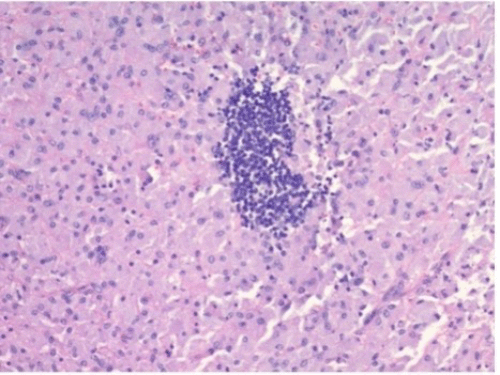

Pathology revealed a spleen measuring 26.0 × 17.0 × 11.5 cm and weighing 2201 grams. Ziehl-Neelsen staining demonstrated macrophages engorged with acid-fast organisms (Figure 2). Grocott methenamine silver (GMS) and periodic acid-Schiff (PAS) stains were negative. Given the positive acid-fast bacilli, disseminated MAC was presumed, and the patient was started on azithromycin, rifabutin, and ethambutol. The patient was discharged with a plan for post-splenectomy vaccinations in clinic.

Figure 2. Histopathological Analysis. Published with Permission

(A) Hematoxylin and eosin (H&E) stain, 10x magnification

(B) H&E stain, 45x magnification

(C) Ziehl-Neelsen (acid-fast bacillus) stain, 45x magnification

Diagnosing MAC infection relies on culturing the organism from a normally sterile body site. While cultures from any such site can be diagnostic, blood, bone marrow, lymph nodes, and liver are the most commonly involved tissues and, thus, the preferred samples for culture.14 The histopathological findings in this case are consistent with disseminated MAC infection. The presence of poorly defined granulomas with pale blue, striated histiocytes harboring mycobacteria is characteristic of this disease.15 While Klatt et al. describe necrotic areas filled with inflammatory cells and nuclear debris as a potential histological feature of disseminated MAC, the observed findings, in this case, support a diagnosis nonetheless.15